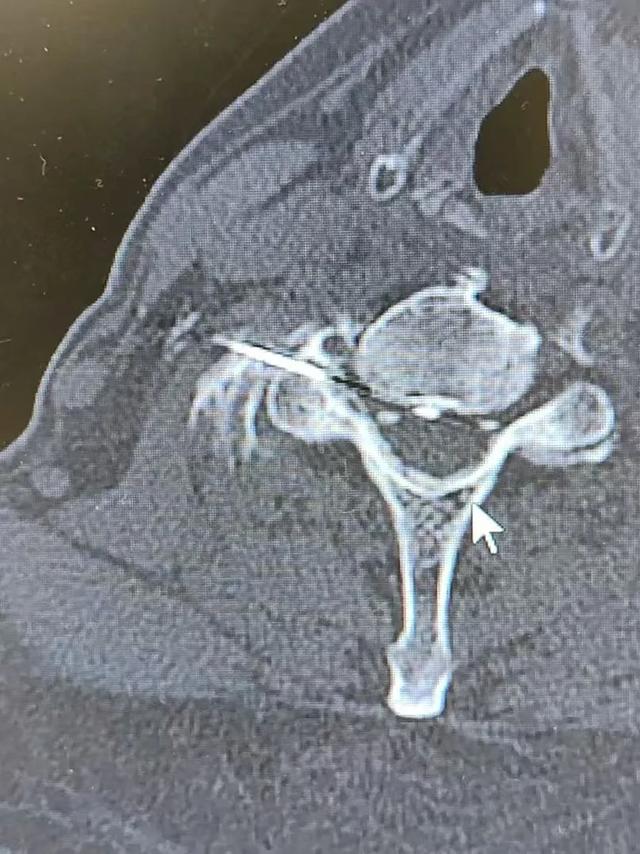

在CT引导下行神经根脉冲射频术

CT引导下颈神经根脉冲射频术(左图),三叉神经半月结脉冲射频术(右图)